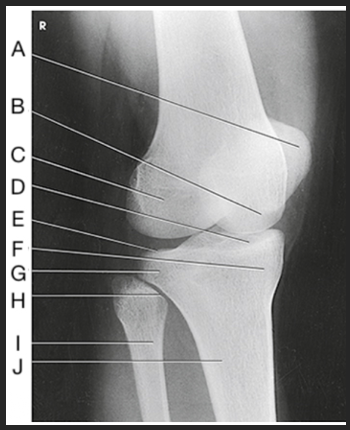

Label the image: A

popliteal surface

Label the image: B

adductor tubercle

Label the image: C

medial epicondyle

Label the image: D

medial condyle

Label the image: E

lateral condyle

Label the image: F

lateral epicondyle